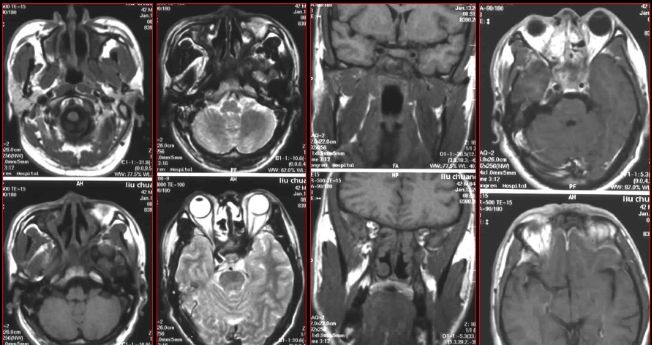

慢性多发鼻窦炎—MRI

MRI表现:

★ 侵袭为黏膜炎性水肿和蜂窝织炎,T1WI为低信号,T2WI为高信号

★ 慢性为明显低信号,钙化,霉菌内含有铁和锰等顺磁性物质,含蛋白质高的黏液等。

★ 反应性肉芽肿或鼻窦炎T1WI为低信号、T2WI为高信号

★ 增强扫描病变周边黏膜明显强化

★ 显示侵犯眼眶、颅底、颅内实质或硬脑膜窦